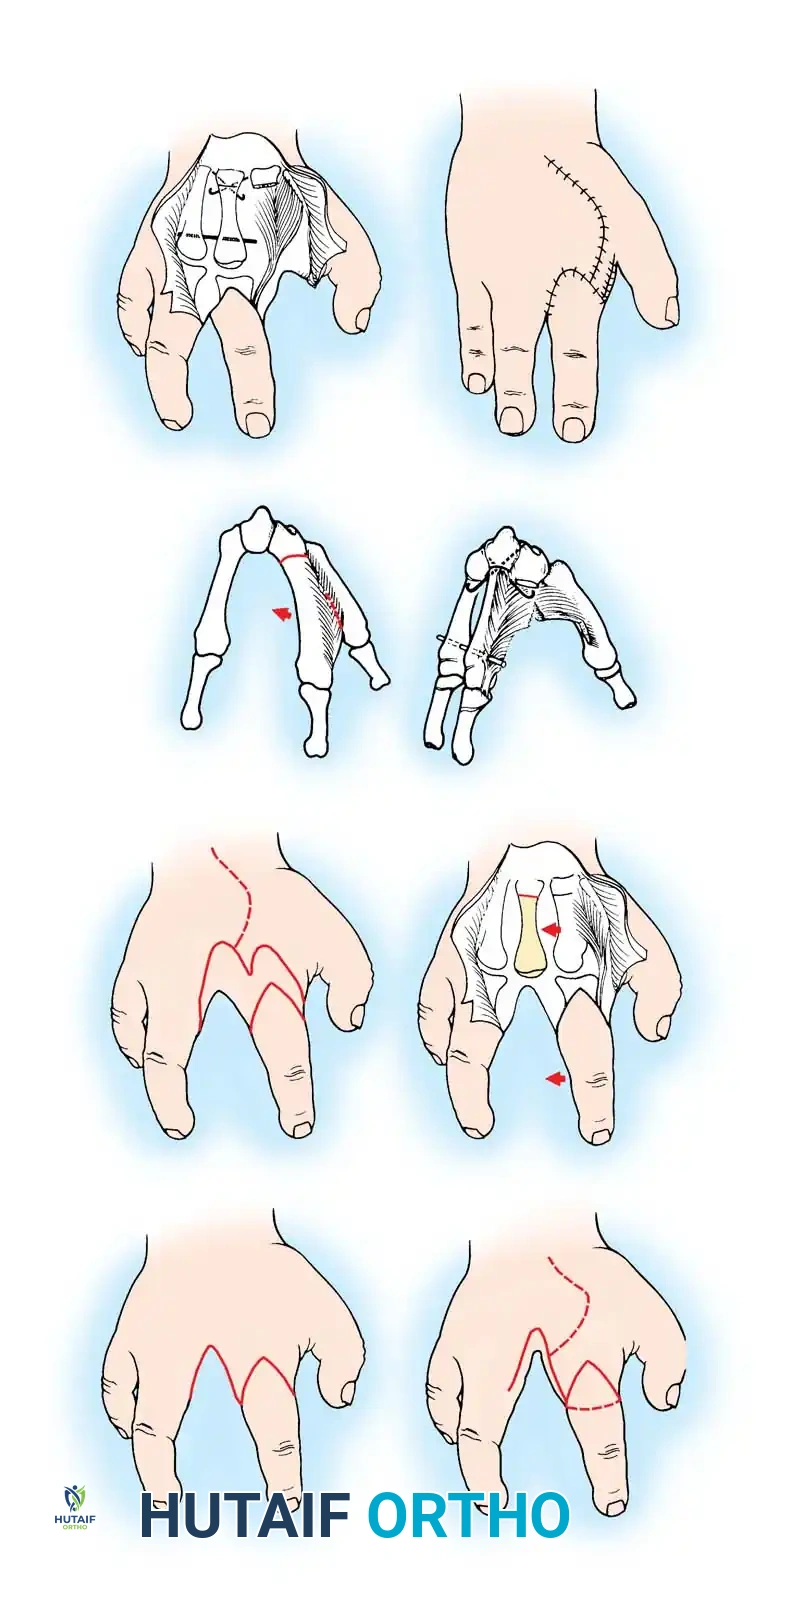

Surgical Interventions in Transverse Deficiencies

Surgical indications for transverse deficiencies are exceedingly rare. Epps, Burkhalter, and McCollough reported that out of 1,077 children

Associated Surgical & Radiographic Imaging